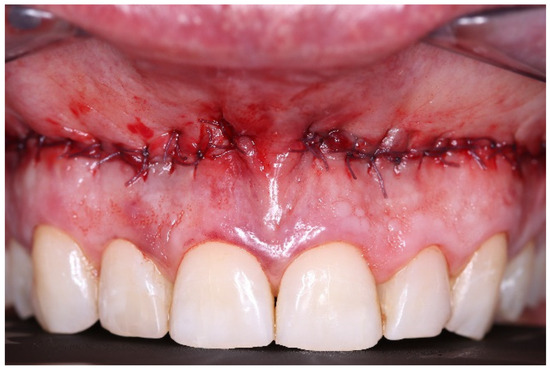

2. Case Presentation